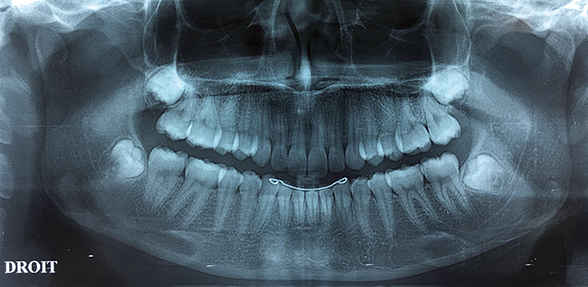

3e MOLAIRE MANDIBULAIRE  INCLUSE ASSOCIÉE À UNE LÉSION OSTÉOLYTIQUE :

Des kystes ou tumeurs associés aux troisièmes molaires incluses sont souvent découverts

de manière fortuite sur les radiographies panoramiques dentaires.

La présence d’une telle lésion constitue une indication d’extraction de la dent de sagesse

et l’exérèse de la lésion pour analyse anatomo-pathologique.